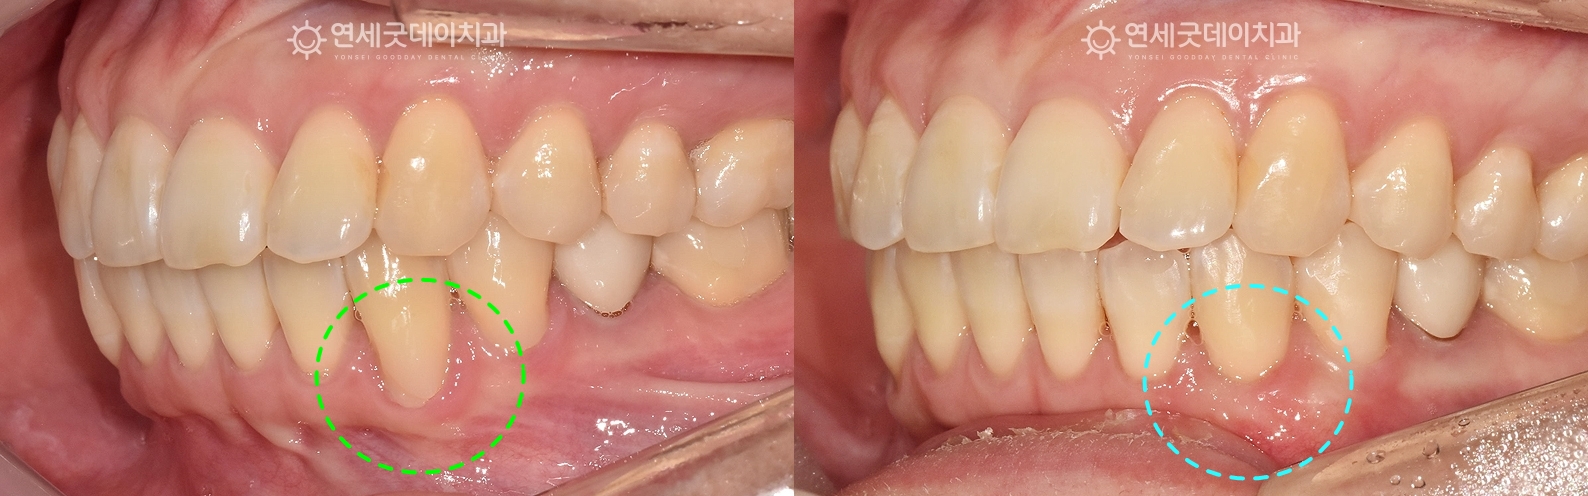

재교정 후 핀홀 잇몸이식, 엠도게인 치료전후 (30대 여성)

좀 더 자세히 보면, 치아 머리는 올바른 위치에 있지만 이러한 경우 치아 뿌리를 잇몸뼈 안으로 재위치 시키고 환자분께 두 가지 치료 옵션을 제안드렸으며 ▼ 환자분께 제안드린 치료 옵션

환자분은 #33 치아의 뿌리 방향을 조절하여 이 과정은 단순히 겉보기 배열이 아닌 11개월 간의 아랫니 부분 재교정을 진행하였으며

환자분의 경우, 치경부 마모를 개선하기 위해 이후 핀홀 잇몸이식과 엠도게인을 병행 적용하여

약 1달 후 경과 모습입니다. 치아가 올바른 각도에 재위치 하면서